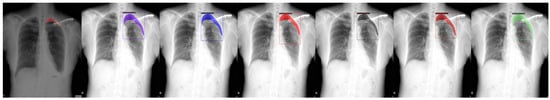

Figure 3.

From left to right: Ground Truth, ResNet50 (COCO), ResNet101 (COCO), ResNeXt101 (COCO), ResNet50 (LVIS), ResNet101 (LVIS), and ResNeXt101 (LVIS). This patient had pneumothorax in their right chest.

Figure 4.

From left to right: Ground Truth, ResNet50 (COCO), ResNet101 (COCO), ResNeXt101 (COCO), ResNet50 (LVIS), ResNet101 (LVIS), and ResNeXt101 (LVIS). This patient had pneumothorax in their top-left chest.

We chose a few examples to demonstrate the capabilities of various models. These images consisted of X-ray images of pneumothorax patients with different areas of disease inflicted. The inclusion of multiple positions and areas in the figures lets us observe the possible outcomes and the differences between the models. In Figure 3 and Figure 6, the patients had pneumothorax on the right side of their chest, with the patient in Figure 6 only affecting the top part, while the patient in Figure 3 had pneumothorax on the outside wall of their right lung. In Figure 4, Figure 5 and Figure 7, the patients had pneumothorax in the left side of their chest, while the patients in Figure 4 and Figure 5 had the upper part of their left lung mostly collapsed, indicating a serious issue of pneumothorax disease. In Figure 5, there are cavity areas at the bottom part, too. In the same image, the ground truth included a portion protruding below the area of the top detection portion due to the late-stage pneumothorax with most of the upper part of the lung collapsing, and all models were unable to detect the cavity of the protruded part. In Figure 7, the patient is seen with a fixation, with the pneumothorax affecting the top left lung, albeit with a smaller area.